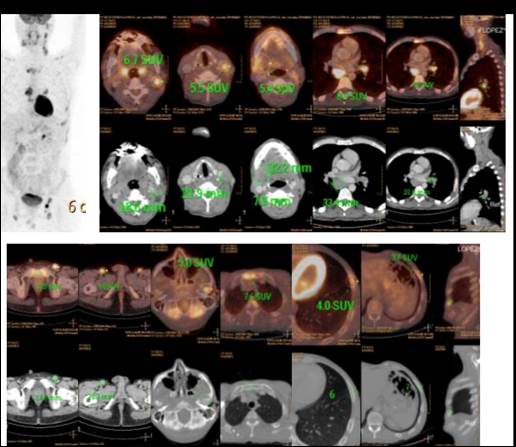

Se completó estadificación con PET-TC. El estudio mostró imágenes de concentración patológica del radiotrazador en múltiples adenopatías hipermetabólicas y en focos hipermetabólicos óseos, que interpretamos como vinculados a compromiso nodal y extra nodal de enfermedad linfoproliferativa (Figura 1).

Figura 1. Hallazgos del PET-TC al diagnóstico

- El paciente presentaba estadio de Ann Arbor: IV B